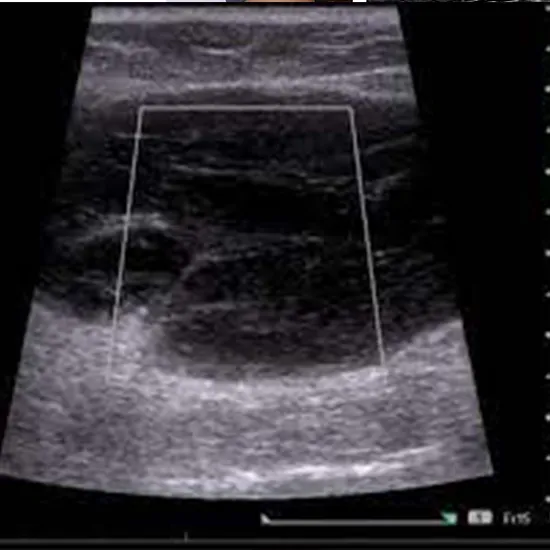

Ultrasound Gluteal Region Test

An Ultrasound Gluteal Region Test is typically performed in a hospital's radiology department or an outpatient imaging facility. So, for the best services and reliable results, schedule your test at Ganesh Diagnostic in Yamuna Vihar.